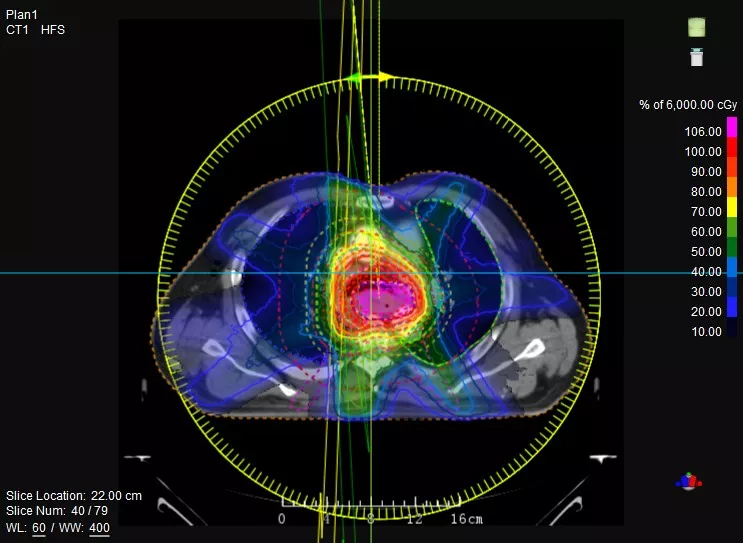

一款設(shè)備即可滿足CT模擬定位、CT影像引導(dǎo)、uARC動(dòng)態(tài)旋轉(zhuǎn)調(diào)強(qiáng)放療等重要臨床應(yīng)用,無(wú)需科室/治療室間切換,一站完成放療全流程。

機(jī)載CT影像可直接用于放療計(jì)劃制作

鼻咽癌患者,進(jìn)行旋轉(zhuǎn)容積調(diào)強(qiáng)治療(uARC)